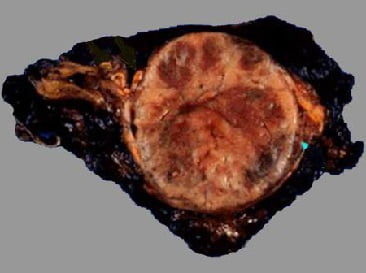

Феохромоцитома, как выглядят больные: фото

На фото ниже показано, как проявляется заболевание у человека.